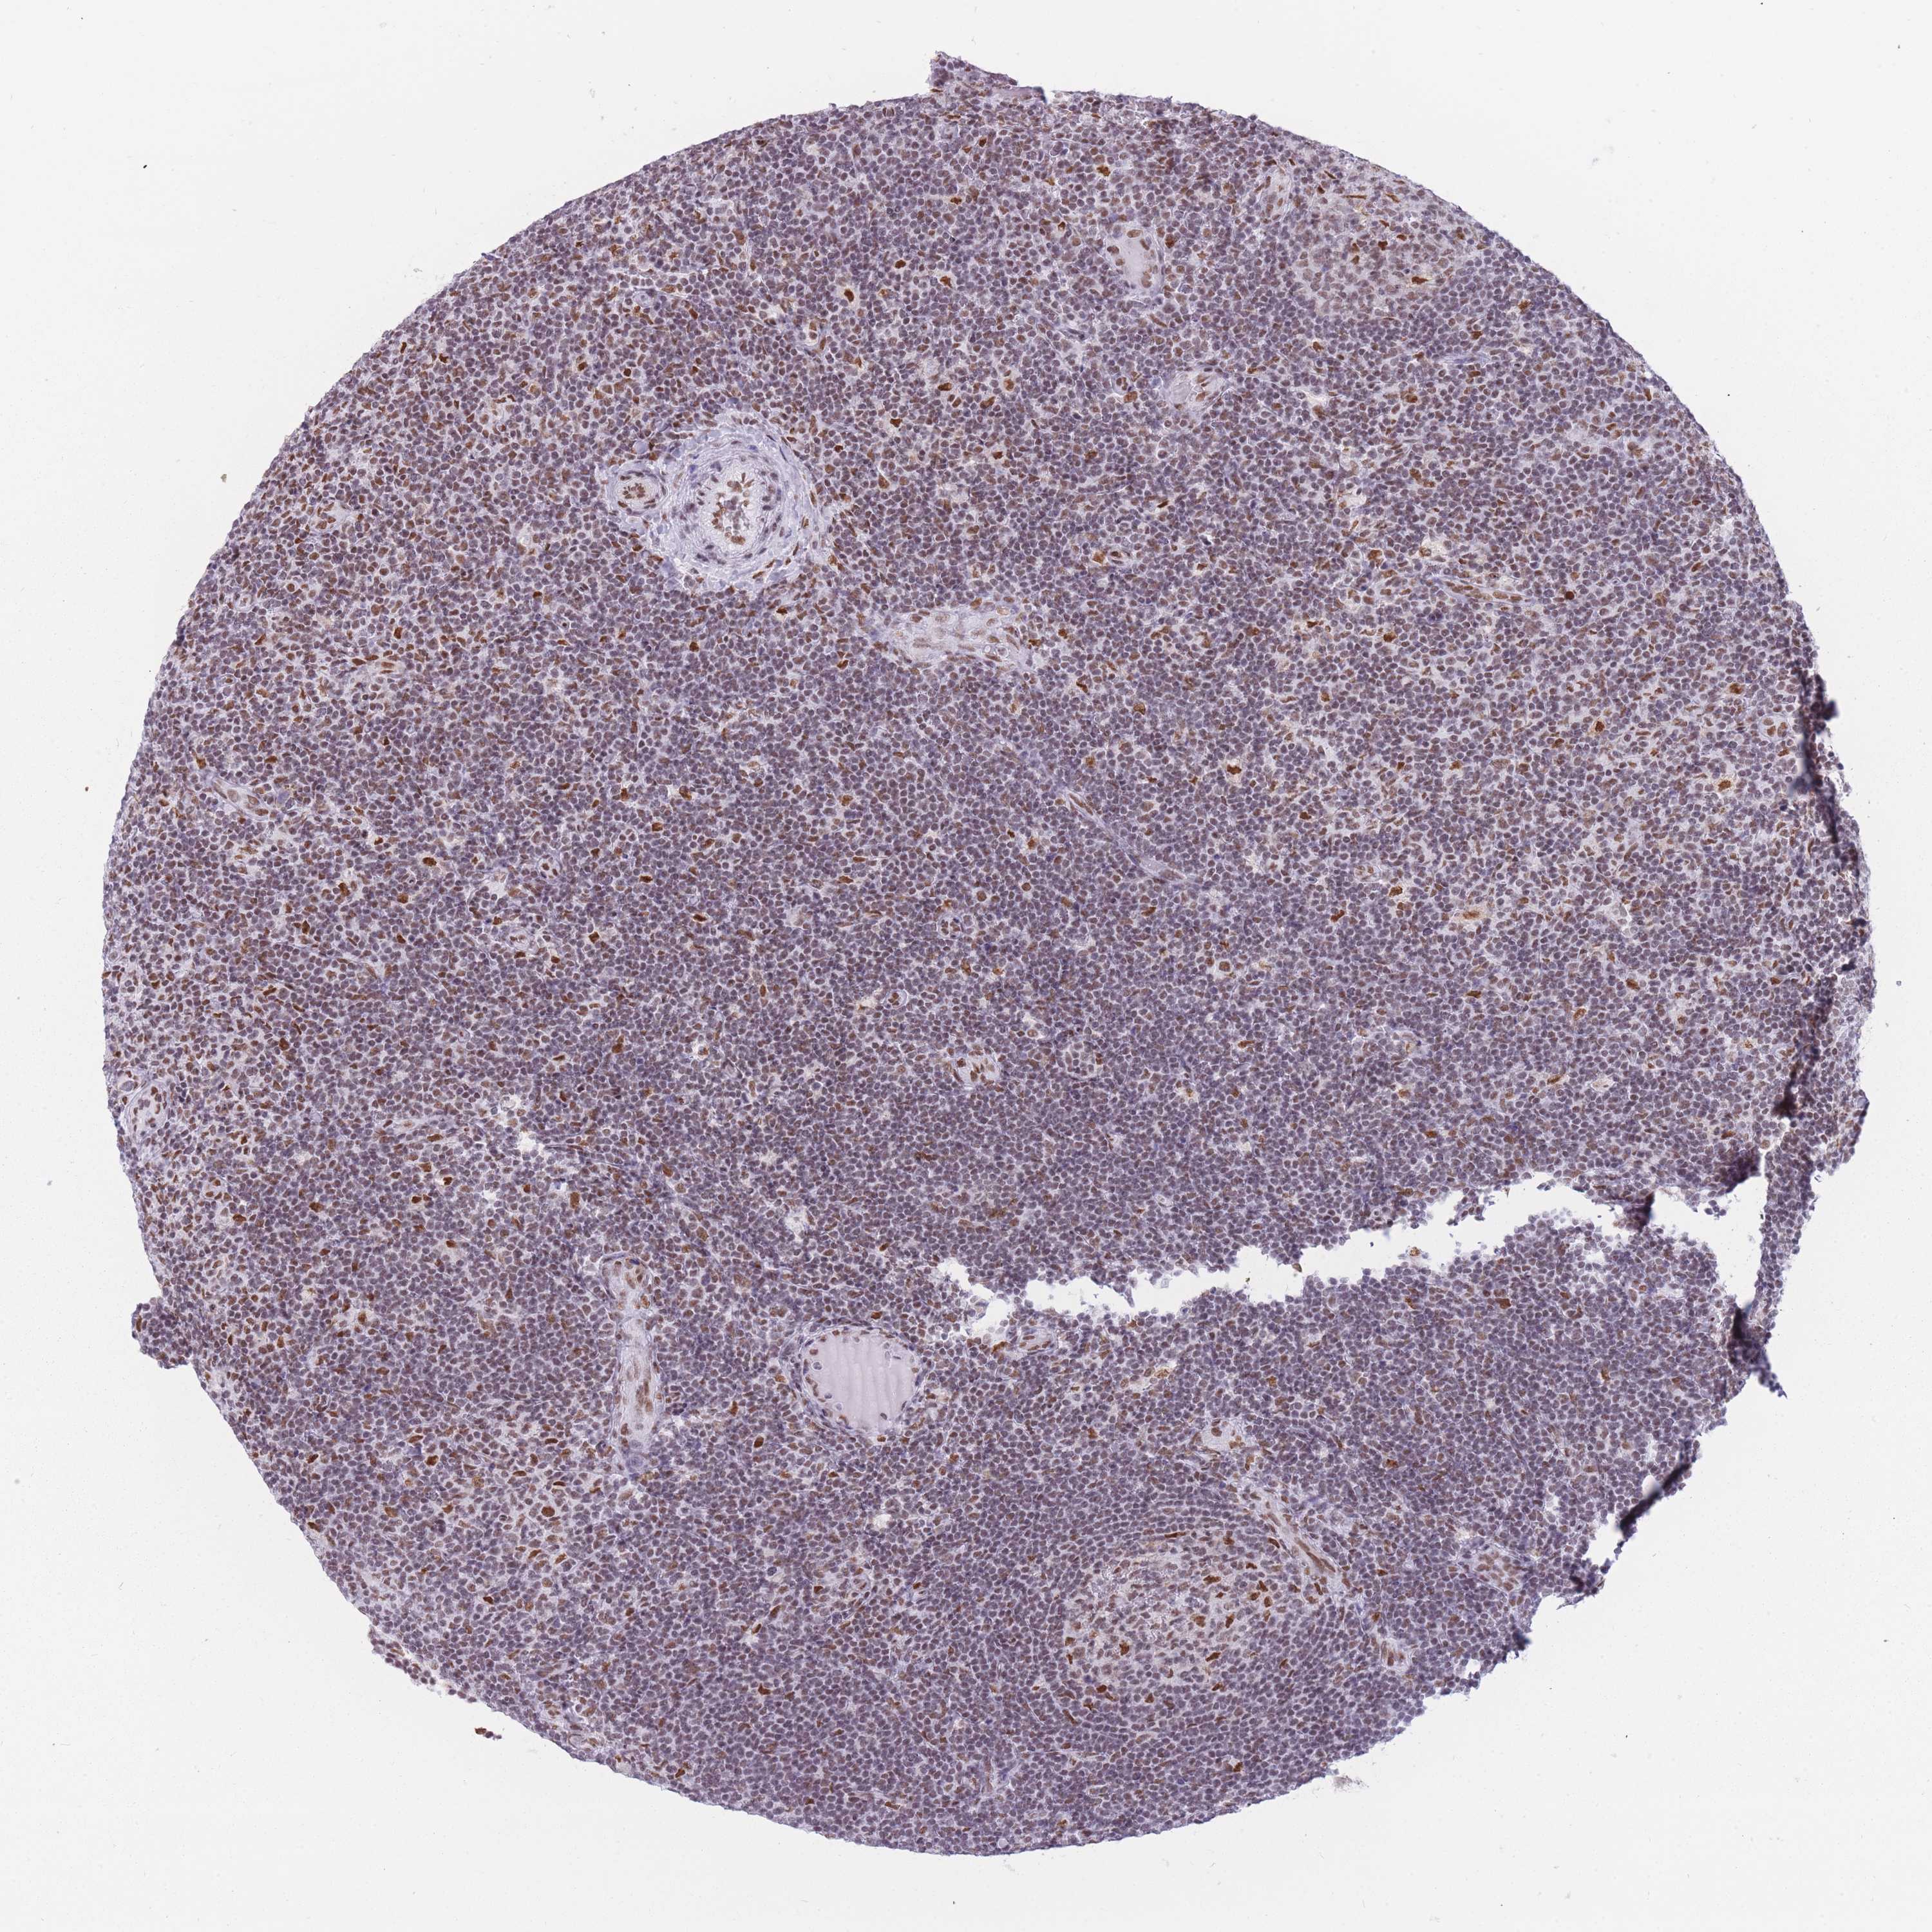

LYMPHOMA - Protein expressioni

A mouse-over function shows sample information and annotation data. Click on an image to view it in a full screen mode. Samples can be filtered based on level of antibody staining by selecting one or several of the following categories: high, medium, low and not detected. The assay and annotation is described here.

Antibody staining in the annotated cell types in the current human tissue is reported as not detected, low, medium, or high, based on conventional immunohistochemistry profiling in selected tissues. This score is based on the combination of the staining intensity and fraction of stained cells.

Each image is clickable and will lead to virtual microscopy that enables deeper exploration of all samples and also displays staining intensity scores, fraction scores and subcellular localization as well as patient and tissue information for each sample.

Antibody HPA049475

Intensity

Strong

Moderate

Weak

Negative

Quantity

>75%

75%-25%

<25%

None

Location

Nuclear

Cytoplasmic/membranous

Cytoplasmic/membranous,nuclear